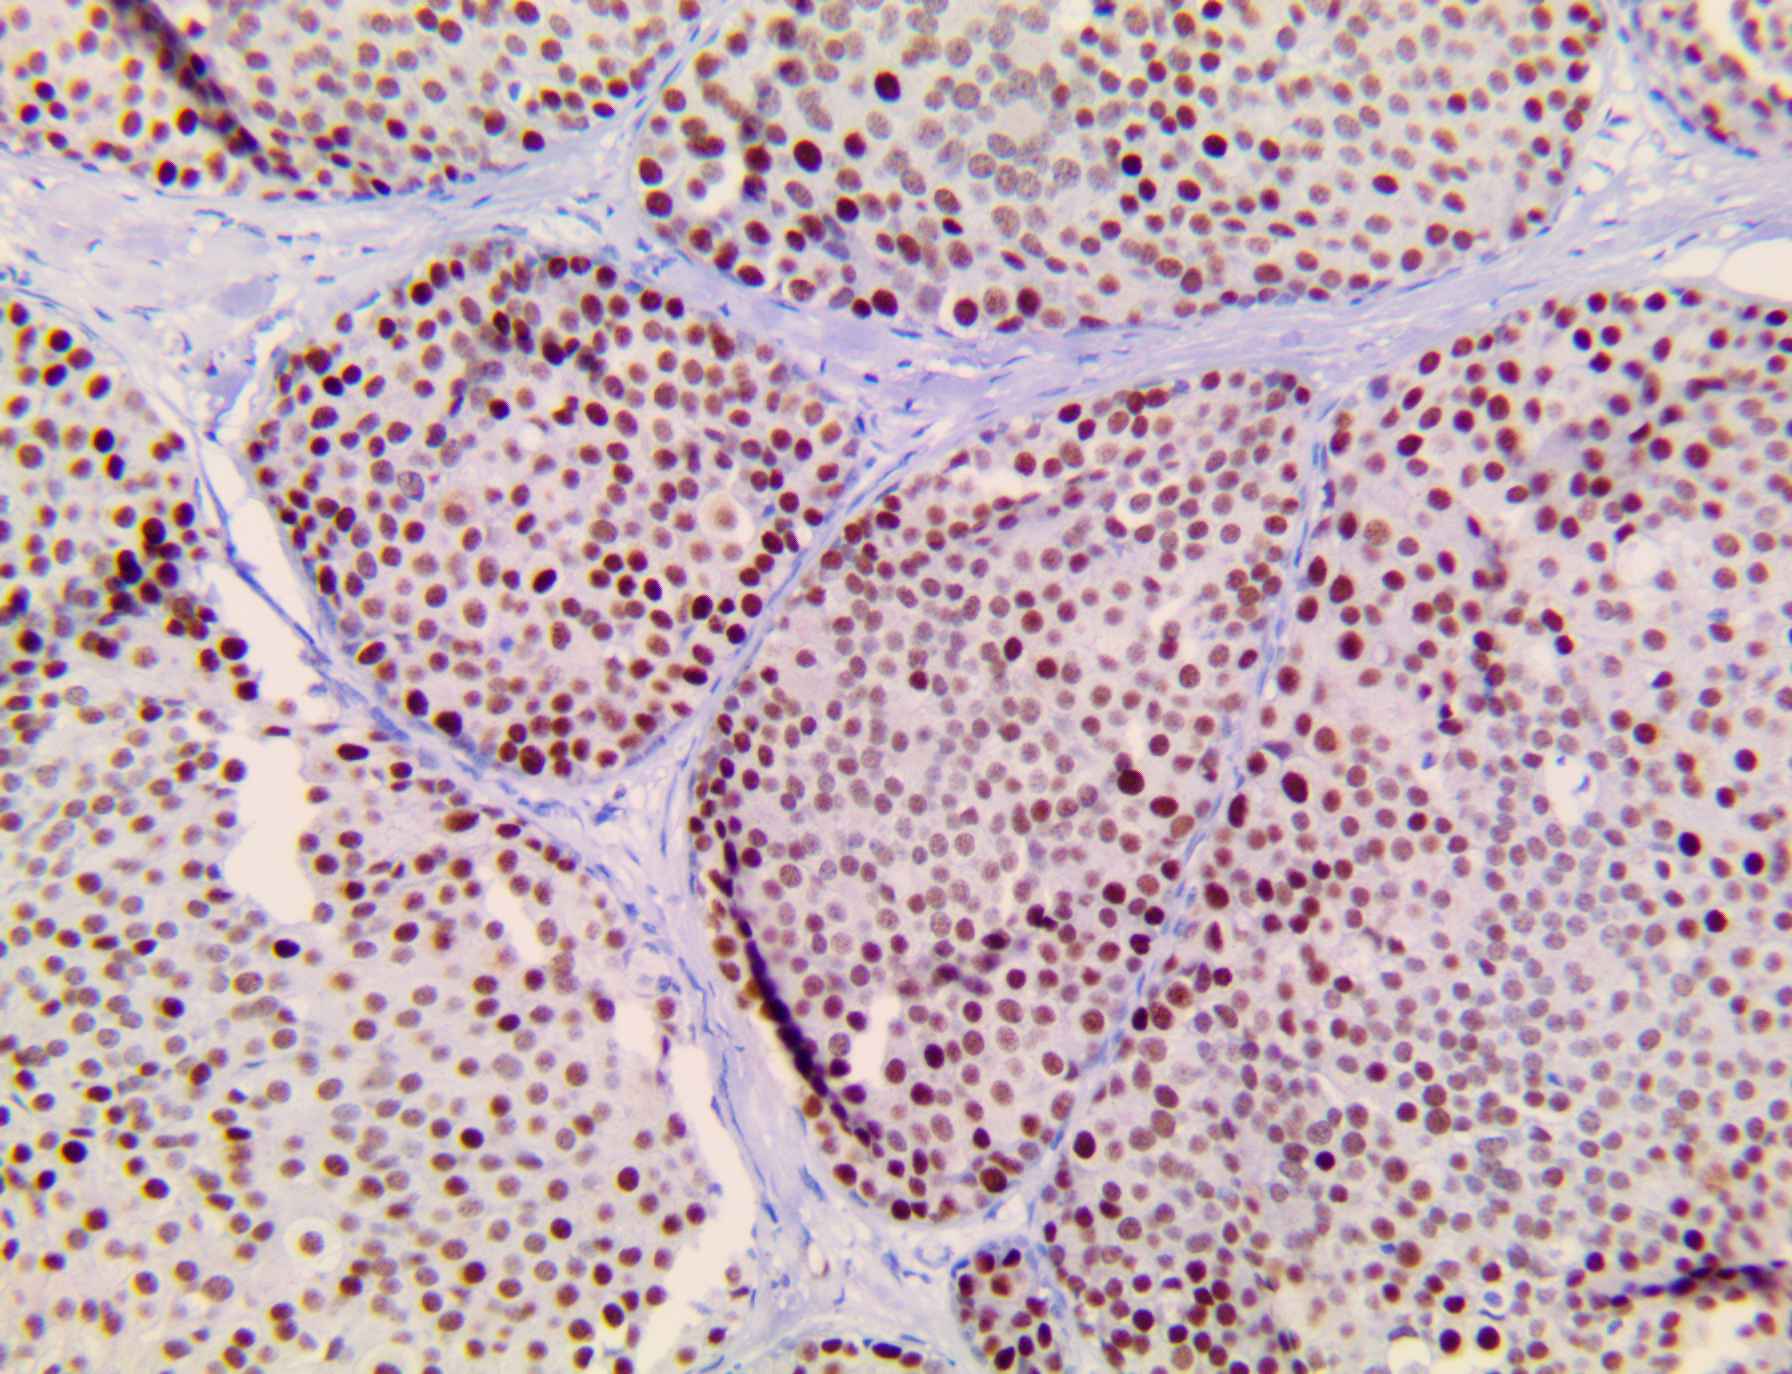

It is the ICU physician who is most likely to witness one of the deadliest manifestations of the abnormal immunological response, the cytokine storm syndrome (CSS). This response is also referred to by some as the cytokine release syndrome (CRS). CSS is characterized by continuous activation and expansion of macrophage and lymphocyte populations, which secrete large amounts of cytokines, causing the cytokine storm. This massive cytokine release is akin to hemophagocytic lymphohistiocytosis (HLH) disease, a syndrome characterized by initial unchecked and persistent activation of cytotoxic T lymphocytes and NK cells.

Clinical and laboratory manifestations of HLH include fever, enlarged liver and/or spleen, neurologic dysfunction, coagulopathy, liver dysfunction, cytopenias (i.e., low levels of erythrocytes, leukocytes, and/or platelets), hypertriglyceridemia, hyperferritinemia, hemophagocytosis, and eventually diminished NK cell activity as the immune system becomes progressively paralyzed. HLH can be familial (primary HLH) or secondary to another disease process (sHLH), such as rheumatic disease, in which it is referred to as macrophage activation syndrome (MAS, characterized by elevated ferritin).